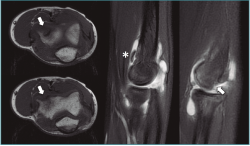

La tomografía computarizada (TC) permite una mejor definición del defecto. La resonancia magnética (RM) muestra edema óseo en las fases más iniciales(1). Además, esta última permite medir el tamaño y la extensión del defecto articular, que es esencial para planificar el tratamiento. En fases iniciales, se aprecian cambios en las secuencias T1 con aspecto normal en T2 (Figura 2). Cuando comienza a fragmentarse, se origina una señal hiperintensa alrededor de la lesión detectable en la secuencia T2, signo demostrativo de inestabilidad. Jans et al.(8) determinaron que la RM tiene una sensibilidad del 100% para diagnosticar una lesión inestable. Además, es extremadamente efectiva para localizar cuerpos libres, que aparecen en el 36% de los casos y que se calcifican con el tiempo, localizándose en la cámara anterior o la gotiera lateral (Figura 3).

Figura 2. Imágenes de resonancia magnética en el plano coronal del codo, donde se aprecia una lesión osteocondral en el capitellum con señal hiperintensa en la secuencia T2 (imagen derecha).

Figura 3. Imágenes de resonancia magnética de una osteocondritis disecante de codo de tipo IV de la International Cartilage Repair Society (ICRS). Se aprecia el defecto en los planos transversal y sagital en la región anteroinferior del capitellum (flechas) y cuerpo libre en la cámara anterior (asterisco).